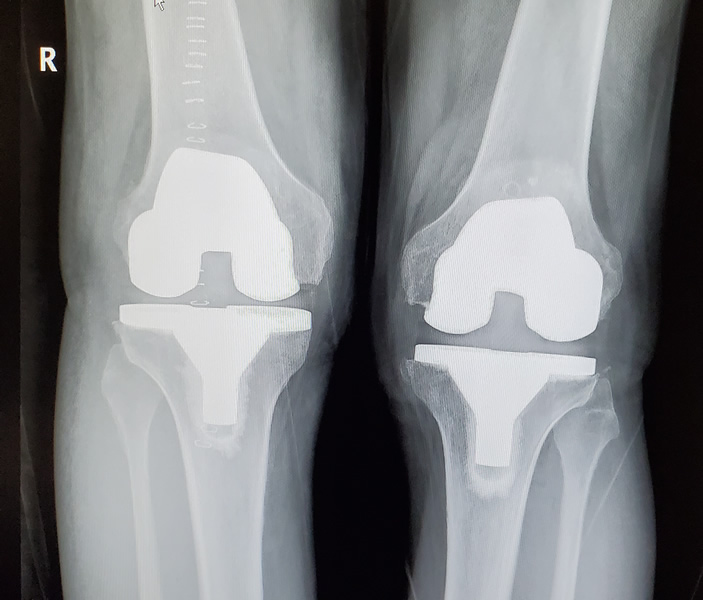

Back to knees….Jim had his left knee replaced on June 25th. Things went smoothly. Our life for more than a few weeks consisted of creating spreadsheets to keep track of Jim’s medicines (we left the hospital with TEN prescriptions!) and updating the calendar to keep track of the Visiting Nurse, In-home Physical Therapy, and in-home blood draws.

It’s now September and the RV is back in storage until January. Jim had his right knee replaced on September 4th. We thought the first knee recovery went fairly well, this knee has been so much easier! We aren’t sure why. Doing all the physical therapy exercises on both legs while healing from the first surgery probably had the second knee strengthened enough that recovery has been easier. Again, after 1 week, Jim was off the walker and using only a cane. We are currently 3.5 weeks post-op and Jim is able to take walks along the Erie Canal. The pain has also been much less. Jim is glad the second knee was easier than the first and not the other way around!

That’s where things stand now. We will stay put until Jim is mostly healed. I say “mostly” because it can take up to a year until all the swelling is gone. But Jim has noticed that when he moves his knees now, they don’t make noise! Come January, we are on the road again, heading to the southwest and warmer weather.

Guess I need to speak with Callie so that she can explain in layman’s terms just what it is she is doing ๐ Nice knees — good surgeon ๐